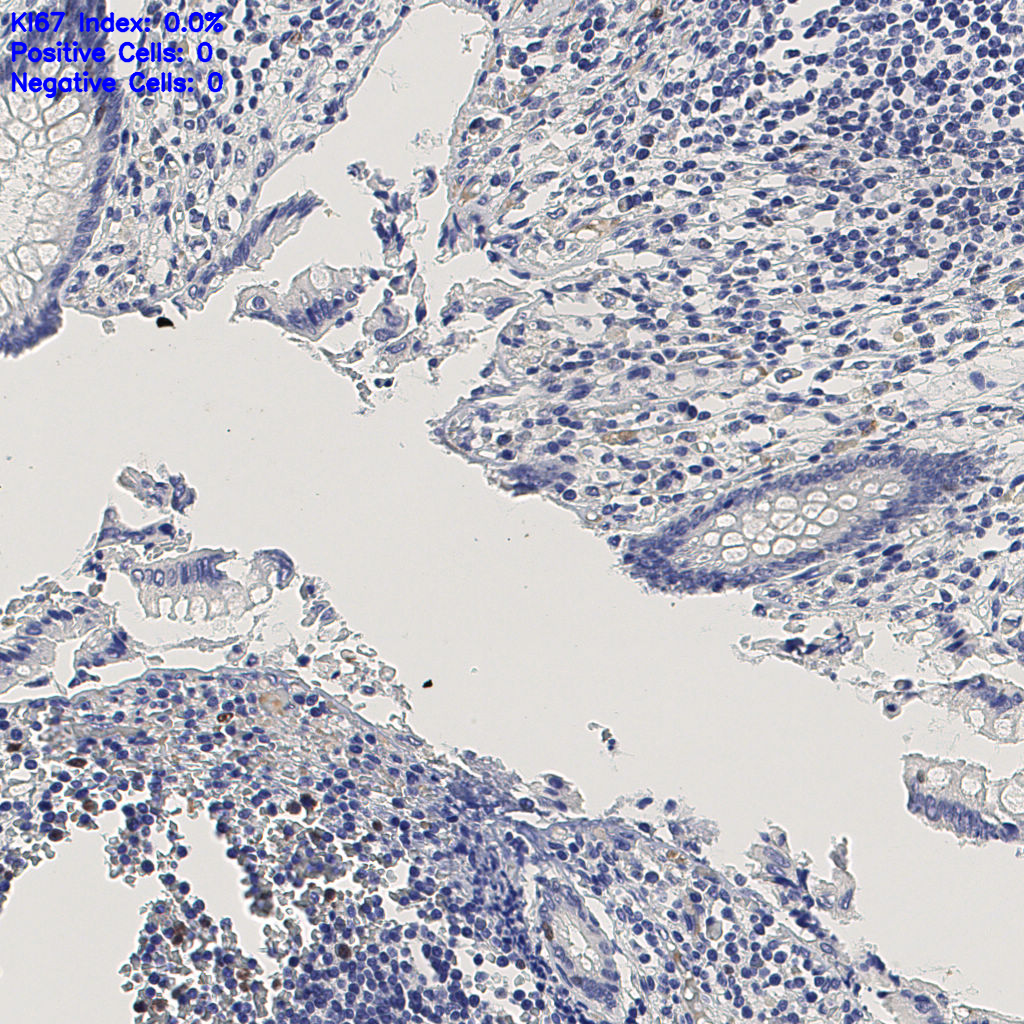

Ki67 指数

阴 1104

阳 94